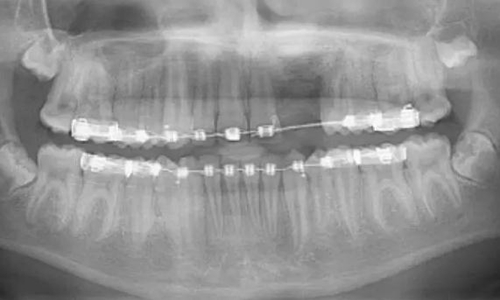

術(shù)后6個月的全景片表明生物性植入材料與天然骨組織之間實現(xiàn)完美平衡[圖5和6]

術(shù)后6年全景片中顯示手術(shù)已為將來種植打下了堅實基礎(chǔ),在此病例中,如果將來進行種植手術(shù),必須等到完全的骨愈合[圖7]